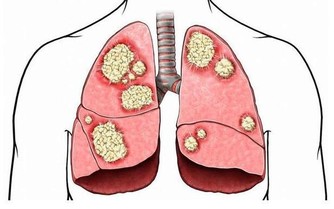

肝臟是人體中排毒解毒的重要器官,也是人體中最大的消化器官,生活中許多肝病患者是由於過度飲酒導致的,過度飲酒會增加肝臟以及腸胃的負擔,肝臟在人體內非常脆弱,起初患肝病,人體並沒有明顯症狀,因此,很多人錯過了治療肝臟最佳時期,當肝臟疼痛的時候,往往代表肝臟已經受損嚴重,生活中我們應該及時發現身體不適,定期去醫院做檢查,及時發現,及早治療。

1、消化不良,口臭

肝臟是人體內最大的消化器官,肝臟受損會影響腸胃消化,尤其是在夏季,食物殘渣會在腸胃間繁殖大量細菌,引起口臭的症狀,如果你沒有腸胃以及口腔方面的疾病,無緣無故的口臭,那麼你要注意是否肝臟出了問題。